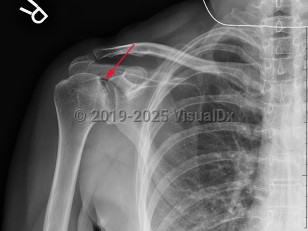

Grade / classification system: Cruess classification

- Stage 3 – crescent sign (subchondral fractures) on x-ray

- Stage 4 – flattening and collapse on x-ray